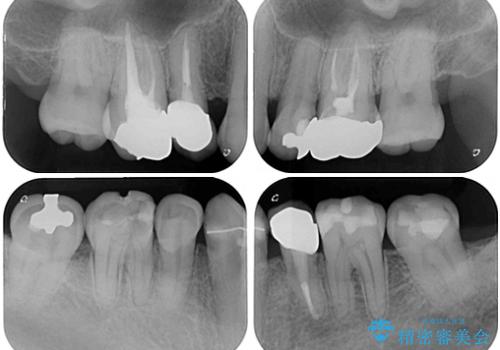

- むし歯による奥歯の痛みを気にして来院された患者様です。

神経にまでむし歯の及んでいる歯や、既に根管治療がされている歯に痛みがあったため、まずは根管治療を行うこととしました。

その後、以前行った抜歯矯正の後戻りをインビザライン・ライトにより改善し、むし歯や銀歯はオールセラミッククラウンにて補綴治療することとしました。